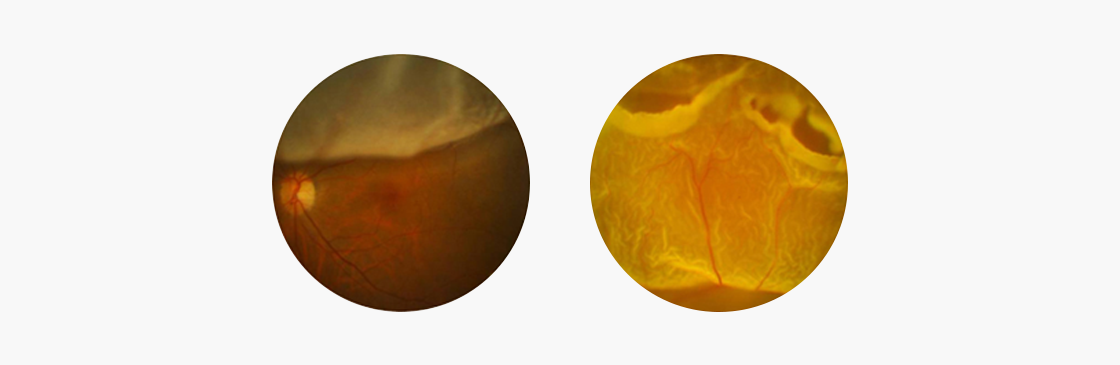

망막박리는 망막색소상피에서 시세포와 내망막층이 분리되는 질환입니다.

망막이 일부 또는 전부가 벗겨지면서 나타나는 질환으로 망막박리가 진행되면 시야의 결손 부위가 점차 커지면서

오래 방치할 경우 실명할 수 있습니다. 망막박리는 보통 고도근시나 노화로 인해 발생할 수 있으며 안구의 종양, 심한 염증 혹은

당뇨망막병증의 합병증으로 발생할 수 있습니다.